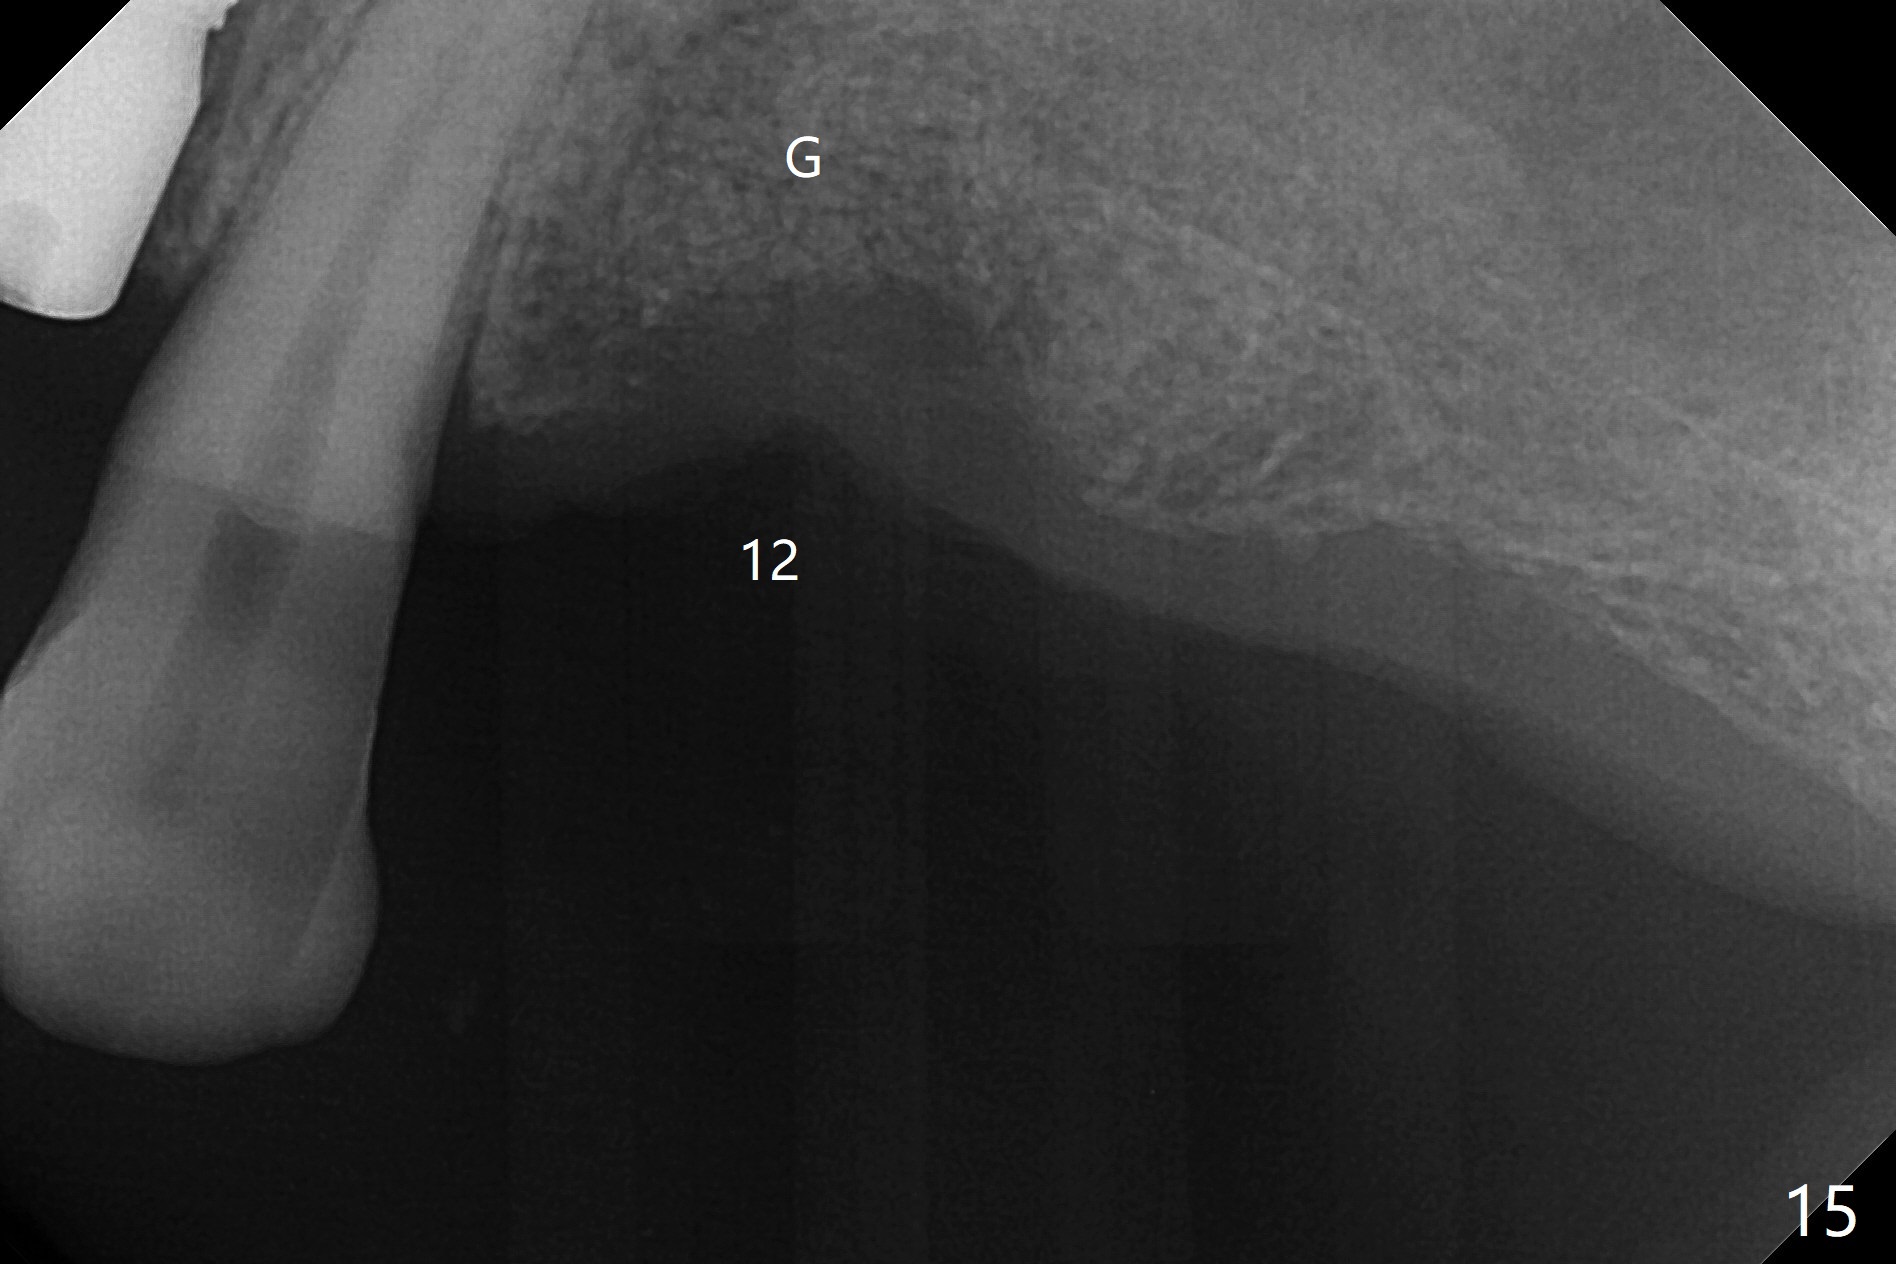

After a 4x10 mm implant is placed with fixture mounting (Fig.2 M) following sinus lift (*) at #12, osteotomy is initiated at #10 (Fig.1 (T: tube of surgical guide)). It appears that the drill (D) has good trajectory (between the Incisive Canal (red dashed line) and the canine root). The final position of the implant at #10 is acceptable (Fig.3). The implant at #12 is placed deeper (Fig.4 (arrow), as compared to Fig.2) because of clinically buccal superficial placement. The most critical challenge is anterior deep bite associated with posterior collapse. Periodontal dressing is applied. When the latter dislodges, there is minimal clearance for a provisional. Periodontal dressing is re-applied. The patient (smoker, partial edentulism with occlusal interference) returns for provisional nearly 1 month postop with chief complaint "something is lost in the back". In fact the healing abutment at #12 is lost with buccal granulation tissue (Fig.5). When a new abutment is seated, there is discomfort. When a healing screw is placed, it cannot be seated completely with two separate trials (Fig.6,7). Should we leave it as it is or open up for complete seating? It appears that the implant is loose. After preparation for clearance at #10, the abutment is retightened. It appears to turn with the underlying implant with discomfort. A 4x5 mm healing abutment is placed to reduce micro-movement. One week later, the infection at #12 dissolves with oral Amoxicillin (Fig.8). Due to limited occlusal clearance and implant tenderness when the abutment abutment is retightened, the cemented abutment is changed to a healing abutment. The implant at #10 seems to be osteointegrated, while the healing screw at #12 remains incomplete seating 3 months postop (Fig.9). The loose healing screw cannot be retightened securely, as there is bone loss around the implant 3 months postop (Fig.10 *). When a 4.5 mm x 15 degree 4 mm cuff angled abutment is placed, the mesiodistal trajectory improves (Fig.11), but there is no occlusal clearance (Fig.12). The latter would form when posterior support is established (Fig.13, either removable appliance (which the patient hates) or fixed one (finance)). Fig.14 shows the unhealed site of #12. Incision confirms the bone loss around the implant, which is removed. Although the sinus floor is absent, there is no membrane perforation. After debridement, allograft mixed with small amount of Osteogen is placed (Fig.15,16 G) and covered with Osteogen plug and 6-month membrane.

The bone density of the site is low 4 months post bone graft (Fig.17,18). Use the existing guide, but incision will be made. The osteotomy will be underprep. Take 5x5 cm CT for bone width and height after use of 2.2x7.3 drill with 1 or 2 O-rings. Prepare sinus lift, including water pump and bone graft, especially distal. Place healing screw and suture. Prepare PRFx2.